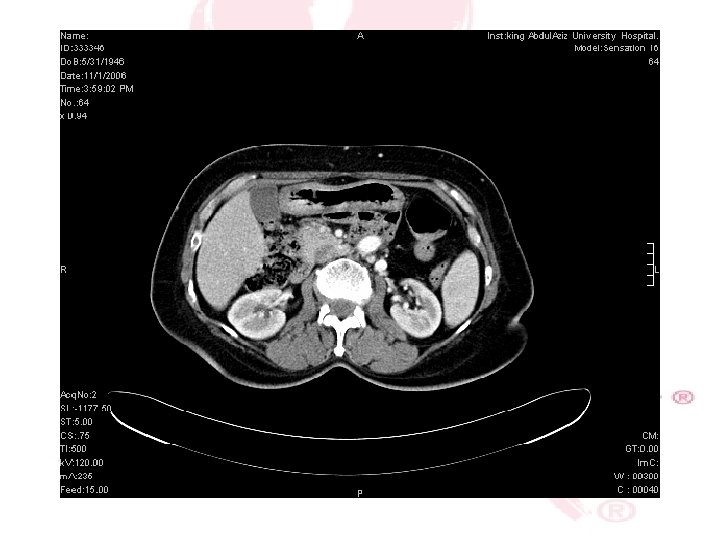

CT SCAN CHEST , ABDOMEN &PELVIS